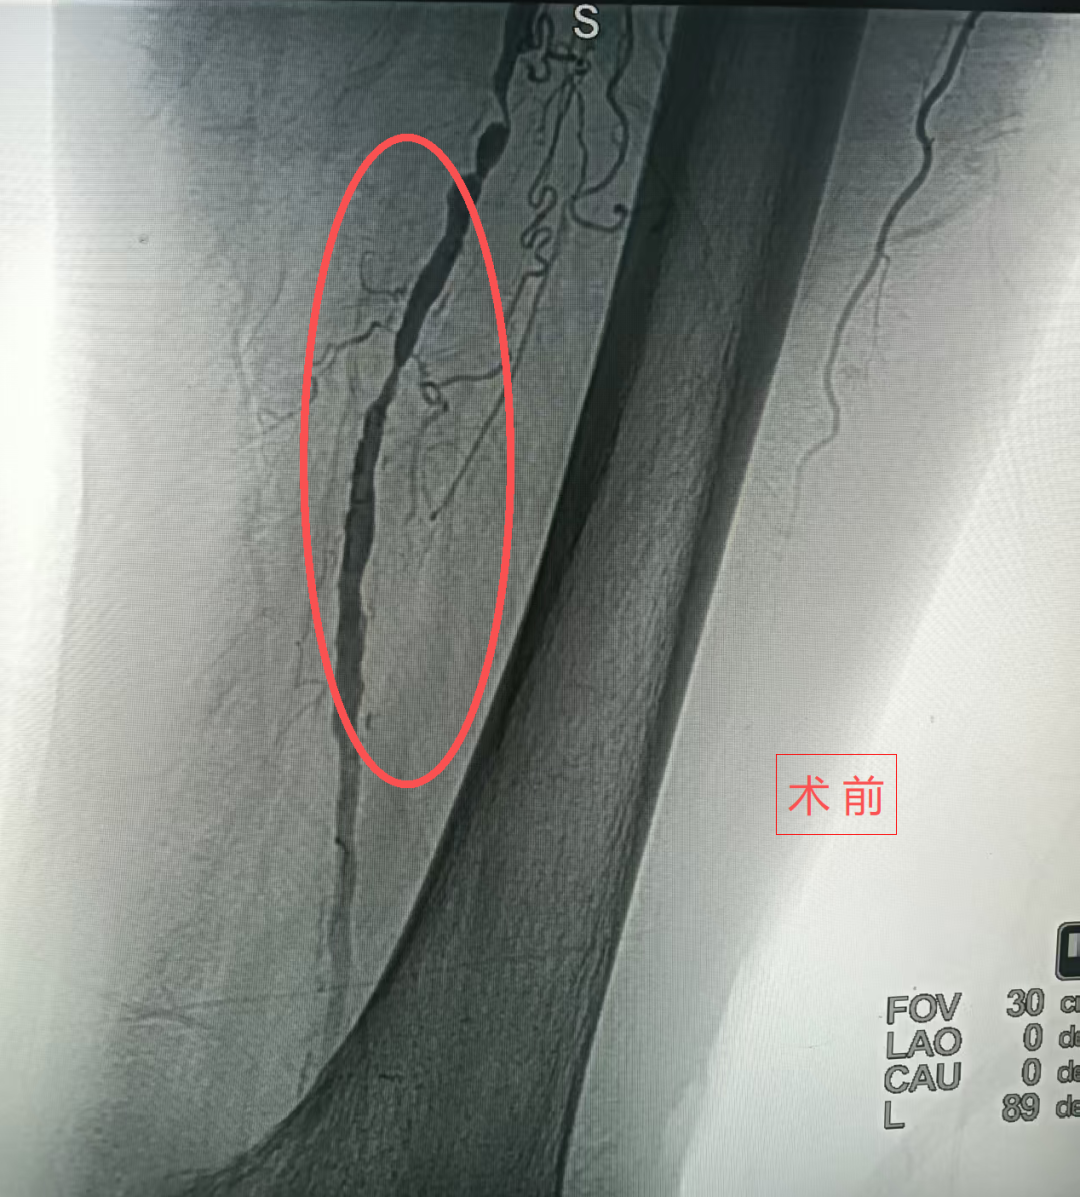

患者为84岁男性,因双下肢持续疼痛、皮肤溃烂一月入院,触诊发现双下肢皮温明显偏低,足背动脉未触及,被确诊为“双下肢动脉硬化闭塞症”。患者既往有脑出血后左侧肢体偏瘫病史,并曾经历腰椎骨折、股骨颈骨折等多次手术,同时伴有慢性肺部疾病,整体心肺功能较差,无法耐受传统开放手术的高风险。

介入手术中,医生在患者左大腿根部进行仅2毫米的穿刺,将球囊导管精准送达闭塞血管部位,通过球囊扩张撑开狭窄段,恢复血流。术中患者全程保持清醒,术后左下肢皮温明显回升,疼痛显著缓解,足背动脉搏动恢复。该项技术避免了全身麻醉风险,减少手术创伤,尤其适合高龄、体弱、合并症多的患者。术后患者恢复迅速,第二天即可下床活动,腿部溃疡也开始愈合。